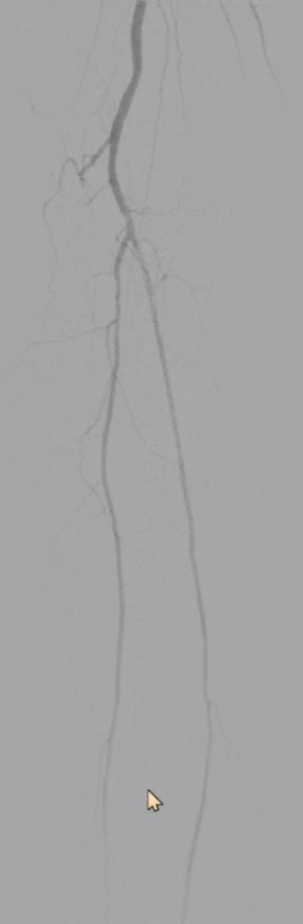

短期疗效

体格检查:右侧胫后动脉恢复正常搏动;

ABI:右侧从术前0.65提升至0.92,缺血症状显著改善。

远期随访(术后半年)

CTA复查:支架内血流通畅,无明显内膜增生,证实手术远期有效性。